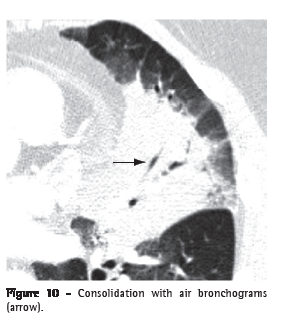

Air bronchogram (broncograma aéreo)

An air bronchogram is the radiological translation of air-filled bronchi, surrounded by sick lung parenchyma, in which the air of the airways has been substituted by any pathological material, radiologically denser than air (e.g., transudate, exudate, blood, accumulation product or neoplastic cells). In general, this is the expression used when a lucent (gas-filled) tubular region is seen within an area of opacified lung (Figures 3 and 10). This tubular image should be of a size and orientation typical of a bronchus or multiple bronchi, presumably representing a segment of the bronchial tree.(22,23)

Consolidation (consolidação)

Consolidation is when the air in the alveolar spaces is supplanted by any type of pathological product, such as inflammatory exudate (pneumonia), transudate (edema), blood (alveolar hemorrhage), lipoprotein (alveolar proteinosis), fat (lipoid pneumonia), cells (bronchioloalveolar carcinoma, lymphoma, organizing pneumonia) or gastric content (aspiration pneumonia).(32) On CT scans, it manifests as increased attenuation of the lung parenchyma, which hinders the visualization of the vessels and outer contours of the bronchial walls. Air bronchograms can be seen (Figures 3 and 10). On CT scans, the attenuation value of the consolidated parenchyma without the use of contrast material is rarely useful for differential diagnosis, with the exception of specific situations (e.g., low attenuation in lipoid pneumonia and high attenuation in amiodarone toxicity).(33,34)

Air spaces correspond to the spaces bounded by the alveolar walls, including the alveolar sacs, alveolar ducts and the alveoli on the walls of the respiratory bronchioles.(43) This term can be used in association with consolidation, opacity or nodules to characterize the origin of such lesions, which fill these spaces with liquid or cells. The air bronchogram sign (Figures 3 and 10) is the trademark of air space filling.